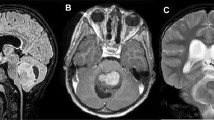

HC in humans can be caused by or is secondary to several factors including structural brain disorders, cilia abnormalities, brain tumors resulting in CSF obstruction requiring CSF diversion, neural tube defects, prematurity and germinal matrix fragility, neonatal systemic and CNS infections, intracranial hemorrhage, evolutionary selection pressures, and ‘genetic’ anomalies, classically thought as Mendelian disorders (Fig. 1). Thus, we conducted a systematic review of human genetic studies of HC to quantify and summarize the current state of genetic contributions to HC of various etiologies (Fig. 2). However, genetic susceptibility confers risk to all these preceding factors as well as to HC directly. Thus, understanding the pleiotropic effect of genes on both risk factors and development of HC is needed and requires highly detailed phenomics analysis [33]. Here, we summarize all genetic studies of human HC across the age spectrum, including discussion of animal models of HC only as corroborating findings of genes and pathways identified in humans where there is a reasonable degree of evolutionary conservation. We believe this is essential as regulation of CSF and brain development is highly divergent across evolution, necessitating clarification and specificity of how genetics plays a role in human disease. Categories are defined a priori based on either phenotypic, molecular, or known genetic classifications. While many forms of HC can reasonably be classified into multiple categories, we attempt to simplify the groupings below.